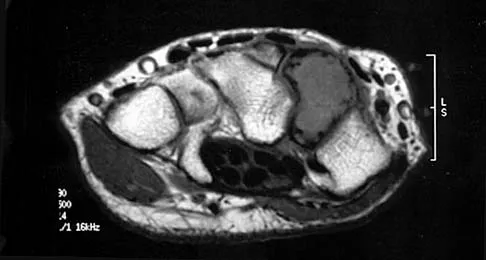

Figures 5a and 5b show axial and coronal MRI images of the left ankle of a patient with lateral ankle pain. What is the most likely diagnosis?

An 11-year-old boy has right shoulder pain and has been unwilling to use the arm after throwing a baseball in a Little League game 3 weeks ago. Examination reveals upper arm and shoulder tenderness with swelling. A radiograph and MRI scan are shown in Figures 27a and 27b. Management should consist of

A 30-year-old man has had intermittent swelling of his right ankle for the past 6 months. He denies any history of trauma. Radiographs reveal osteolytic changes on both sides of the joint. An axial CT scan and a T2-weighted MRI scan are shown in Figures 40a and 40b. He undergoes surgical excision. An intraoperative photograph and a biopsy specimen are shown in Figures 40c and 40d. What is the most likely diagnosis?